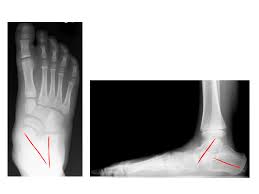

Knick Senkfuss Gesellschaft Fur Fuss Und Sprunggelenkchirurgie E V

Knick Senkfuss Gesellschaft Fur Fuss Und Sprunggelenkchirurgie E V from www.gesellschaft-fuer-fusschirurgie.de

Häufig wird ein knicksenkfuß bei kleinkindern beobachtet, welcher jedoch im rahmen der physiologischen entwicklung des kindlichen fußes als normal angesehen wird und sich bis zum. Der kindliche knicksenkfuß stellt beim säugling und kleinkind eine normalform des fußes dar. Das fettpolster im bereich des sich später entwickelnden längsgewölbes ist beim säugling stark. Gemeinsschaftspraxis rockenhausen sebastian bußmann diabetologie podologie knicksenkfuß knicksenkfuß. Der knicksenkfuß, diagnose und möglichkeiten in der therapie. Zwischen den zwei begriffen gibt es keine klare abgrenzung. Der knicksenkfuß | die knicksenkfüße. Bei dem längsgewölbe handelt es sich um die wölbung, die sich zwischen dem vorderfußballen.